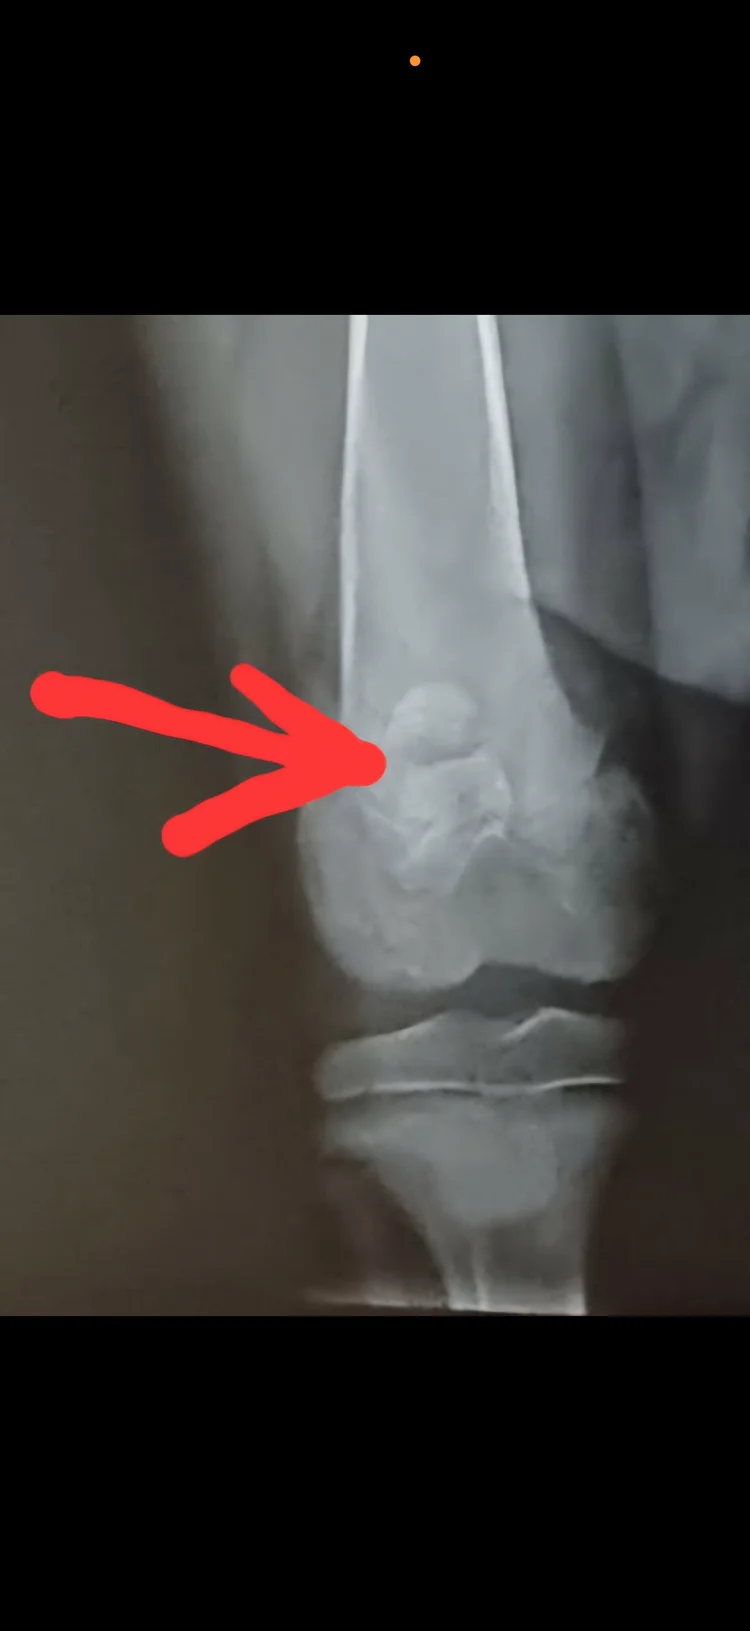

hei jeg har ei border collie tispe stella(13 uker) som har fått ledd skade i høyere bakfot og har nå behov for operasjon av ortoped og rehabilitering etter operasjonen for og kunne få et bra liv igjen å kan være en brukende gjeterhund når hun blir stor. Jeg har ikke penger til full rehabilitering og jeg setter stor pris på alle type bidrag som kan redde henne for at Stella hunden kan få et bra liv igjen. Det er veldig tøft for meg og vite at når valpen min nesten nettopp har startet livet sitt så må avlivning vurderes hvis jeg ikke har råd til rehabilitering for henne